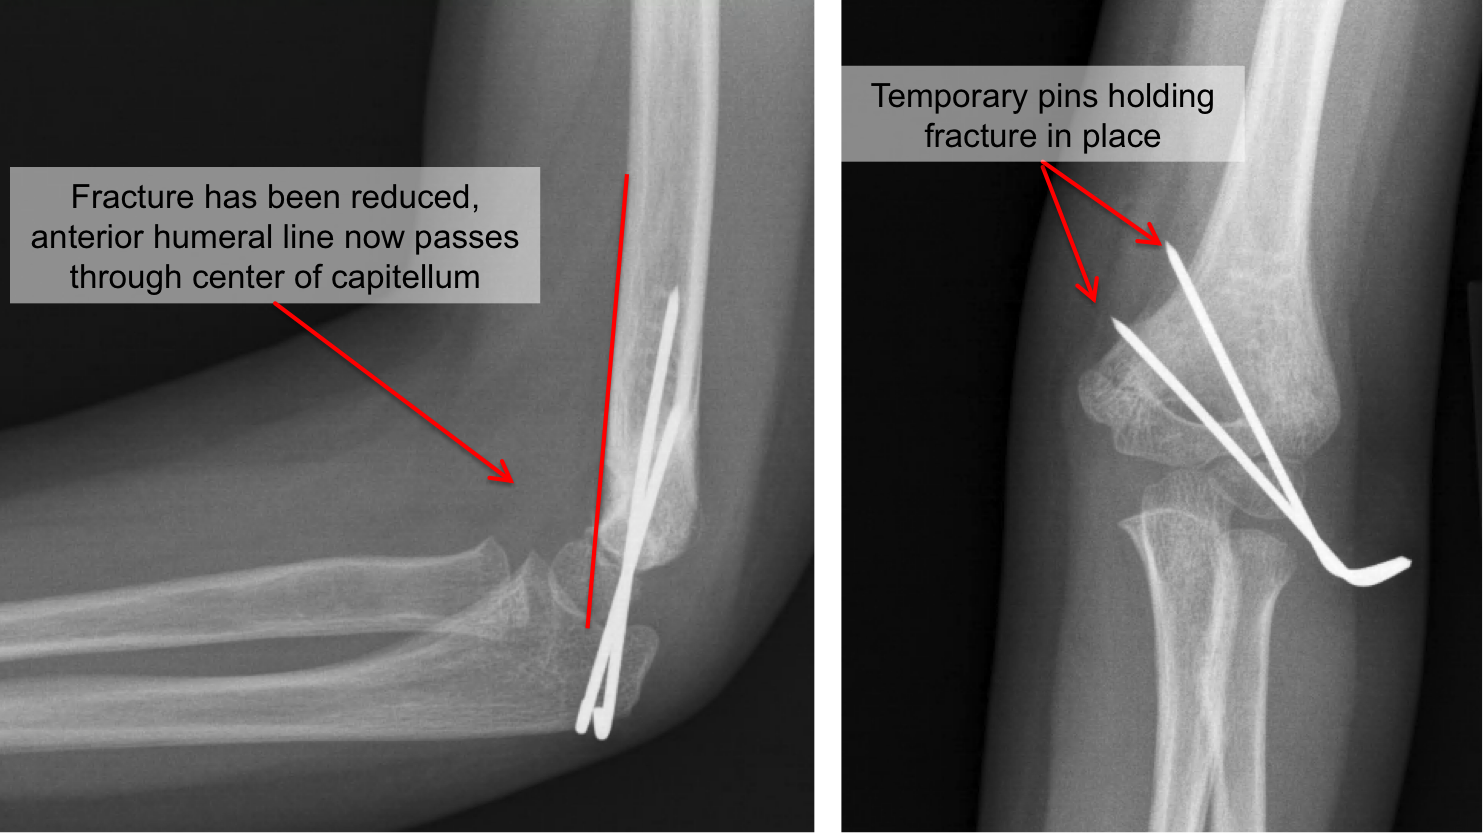

Kid's Elbow Fracture Raleigh Hand Surgery — Joseph J. Schreiber, MD

OrthoKids Percutaneous Pinning Pins In Elbow Removal pins can be used as reduction tools and as fixation devices to achieve proper length, alignment, and rotation. Remove all involved pins and place. how are the pins removed? elbow pins are usually removed in the office in a matter of seconds. in an external fixator, metal pins or screws are placed into the bone through. Pins In Elbow Removal.